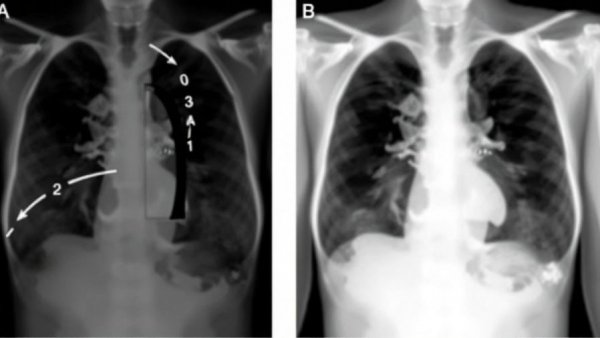

The correlation between the metrics derived from ABVS and VTIQ parameters and their efficacy in predicting axillary lymph node metastasis is crucial. The recent research published in Frontiers in Cell Development Biology classified patients into two groups based on their metastatic status, revealing significant independent risk factors. A maximum diameter of metastatic nodes, the presence of a diagnostic ‘lotus root sign,’ and shear wave velocity showcased strong correlations with higher metastatic burdens. Such precision enables oncologists to tailor treatment strategies effectively, paving the way for more personalized therapeutic approaches.